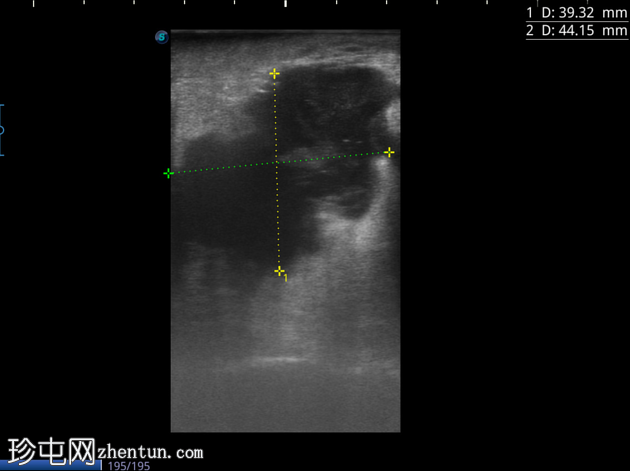

4-10点钟平面

浅表探头

在右前外侧肛周区域(具体位置为10-11点钟方向,紧邻肛壁)观察到一个边界清晰、大小约为5 x 5厘米的低回声病变。病变壁不规则,后部回声增强。病变内部回声提示可能存在肛周脓肿。

在此阶段,未见内部瘘管或与肛管的交通。此外,未检测到明显的病灶周围血管或气体灶。为了更好地评估病变的定位和范围,除了浅表探头外,可能还需要深层探头。